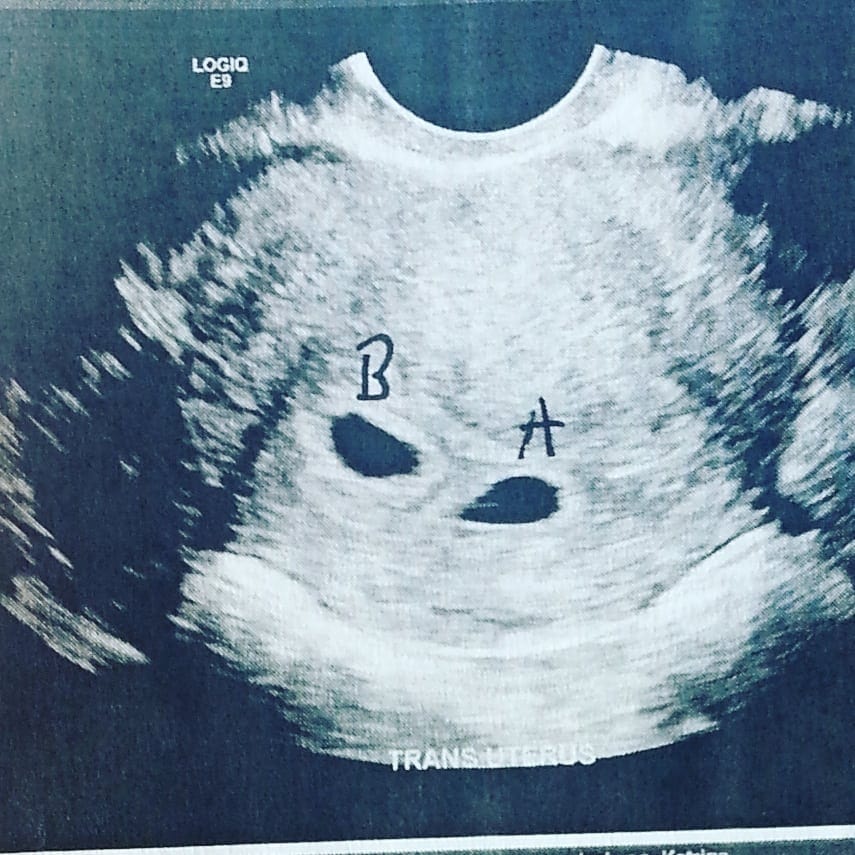

5 Weeks Pregnant with Twins – Twiniversity

4-5 week scan. Is it twins? Anyone had a similar scan and end up with …

How an Ultrasound Can Reveal If You Are Carrying a Hidden Twin | Twins …

Did You Find Out It Was Twins At Later Ultrasound? Twin Ultrasound …

Ultrasound showing foetal development of fraternal twins at 7 weeks …

Ultrasound Photos from the Early Weeks of Pregnancy | Photos, Triplet …